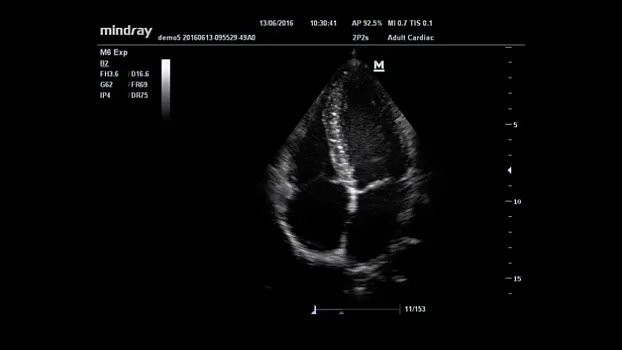

Клинические изображения

2P2s |

Секторный фазированный датчик для кардиологических, транскраниальных и абдоминальных исследований |